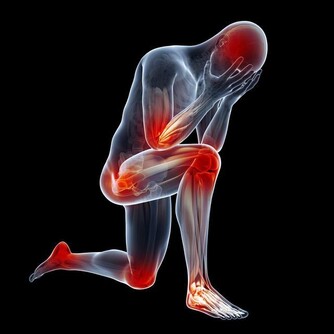

殊不知,冷空氣對關節的損害是很大的,如果不注意保暖,上了年紀很容易患上關節炎。

當人體遇冷時,血管收縮,血流速度減慢,血液中輸送的人體所需的各種養料和氧氣就會減少,而膝關節支撐人的身體,本身周圍血管少,血流速度就差,若穿著短褲、短裙則會使膝關節暴露在低溫環境,膝關節長時間受寒涼刺激,血液循環更慢,更易出現水腫和炎症改變,導致滑囊炎、滑膜炎等關節性疾病。